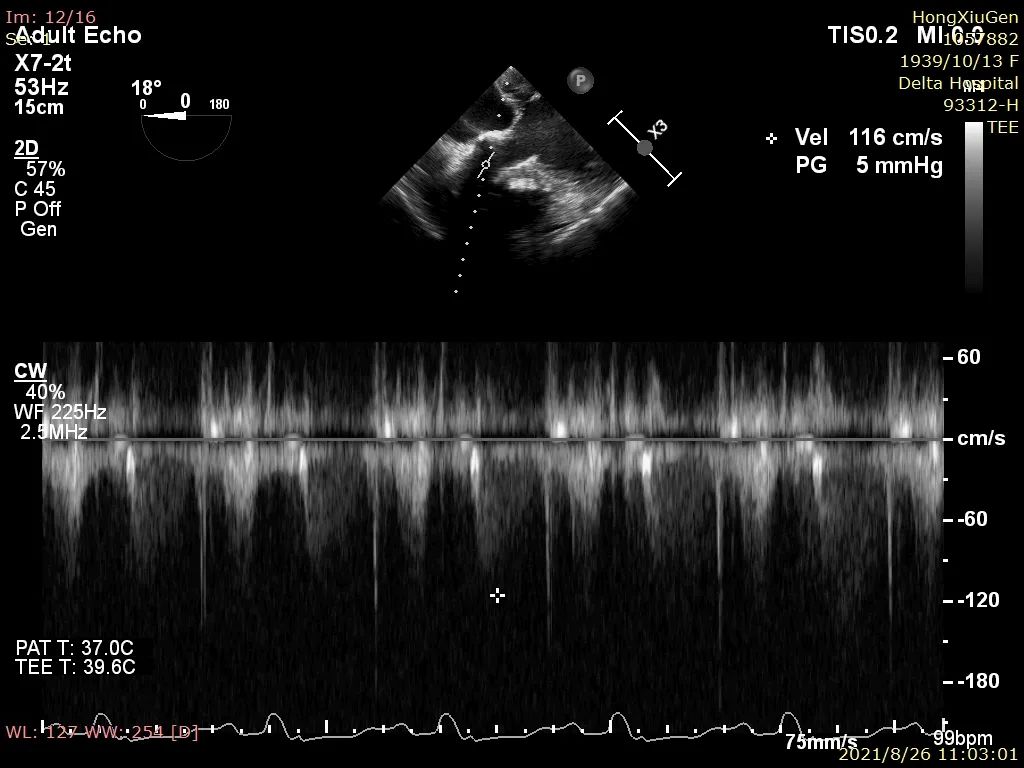

9、超声评估示平均跨瓣压差约5mmHg、微量瓣周漏,造影未见明显反流影;